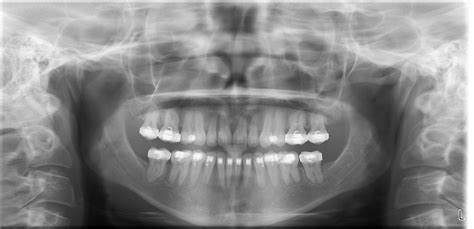

When you visit a dentist for a comprehensive oral health assessment, you might be asked to undergo a specific type of imaging known as a panoramic Xray teeth scan. Unlike standard bitewing X-rays that focus on a few teeth at a time, this diagnostic tool captures a wide-angle view of your entire mouth, including the upper and lower jaws, the temporomandibular joints (TMJ), and the surrounding bone structures. Understanding what this procedure entails can help alleviate any anxiety you might feel before your dental appointment, as it is a safe, painless, and highly efficient way for your dentist to gain a complete picture of your oral health.

💡 Note: A panoramic X-ray does not provide the same level of detail as a periapical X-ray regarding individual cavities between teeth, which is why dentists often combine both types of imaging for a complete diagnosis.

It is helpful to understand how panoramic imaging compares to other common diagnostic tools. The following table illustrates the key differences to help you understand why your dentist might order a specific scan.

Feature Bitewing X-ray Panoramic X-ray

Scope 4-8 teeth Entire mouth

Primary Use Cavities between teeth Jaw, TMJ, and impacted teeth

Patient Experience Sensor inside mouth Outside the mouth

Radiation Level Very Low Low